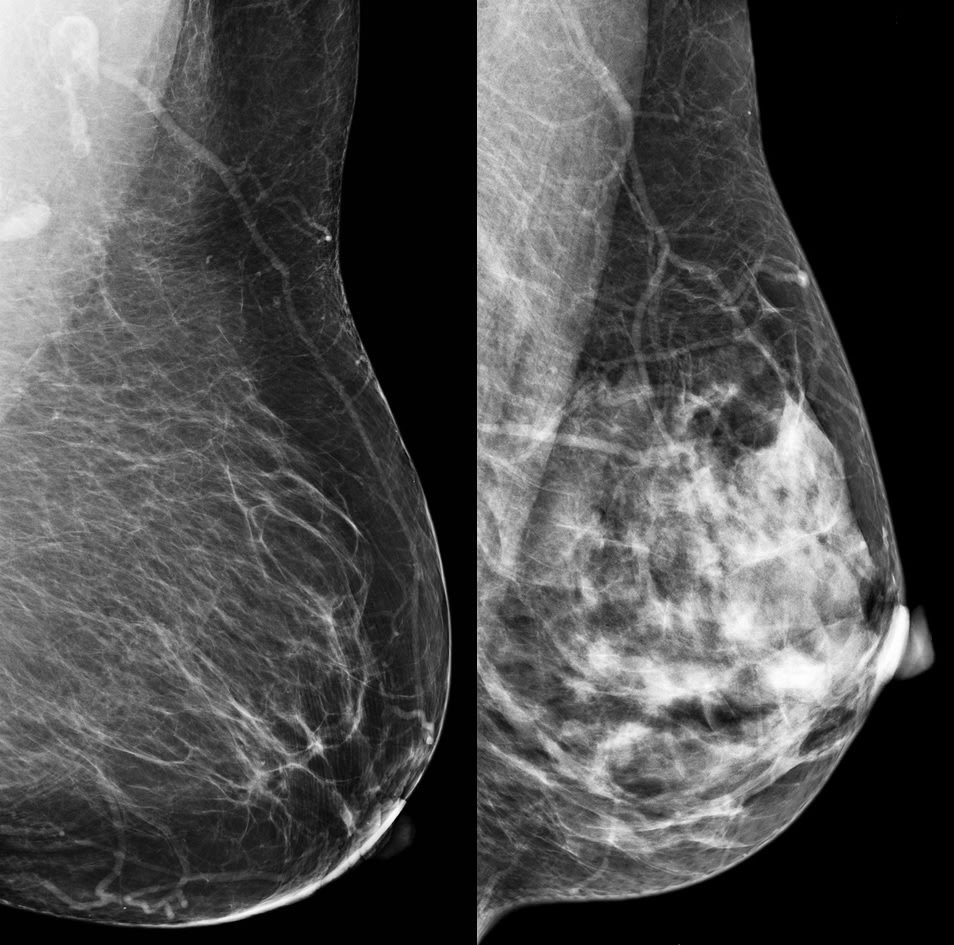

Dense breasts are normal and found in about half of women undergoing mammograms, however, the extra glandular and fibrous tissue can make tumors more difficult to see on mammograms.

A mammogram shows how dense your breasts are. When you get the results of your mammogram, you may also be told if your breasts have low or high density.

Breast density reflects the amount of fibrous and glandular tissue in a woman’s breasts compared with the amount of fatty tissue in the breasts, as seen on a mammogram.

Dense tissue can hide cancers. Fibrous and glandular tissue looks white on a mammogram. So does a possible tumor. Because it’s hard to tell the difference between a tumor and dense breast tissue on a mammogram, a small tumor may be missed.